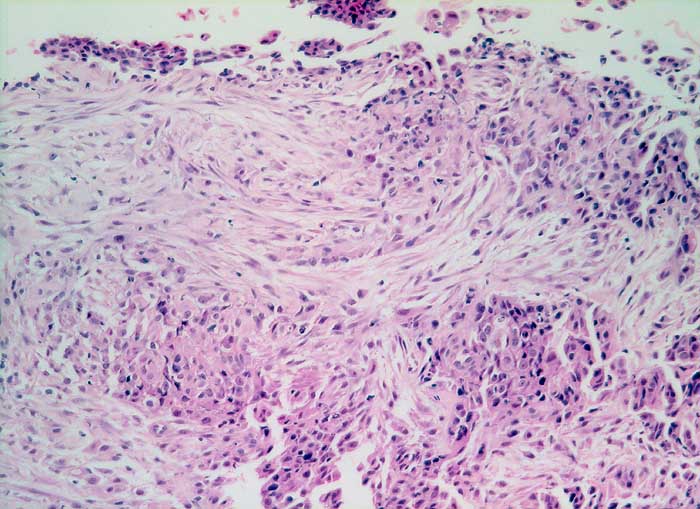

PathoPic ID 5894 - malignes Pleuramesotheliom Mischtyp

malignes Pleuramesotheliom Mischtyp

maligner Tumor

Pleura

Körperhöhlen, Serosa

Der Tumor besteht aus einer sarkomatoiden spindelzelligen Komponente und einer überwiegend soliden epithelialen Komponente aus kubischen Zellen mit hyperchromatischen Kernen.

Histologie

160